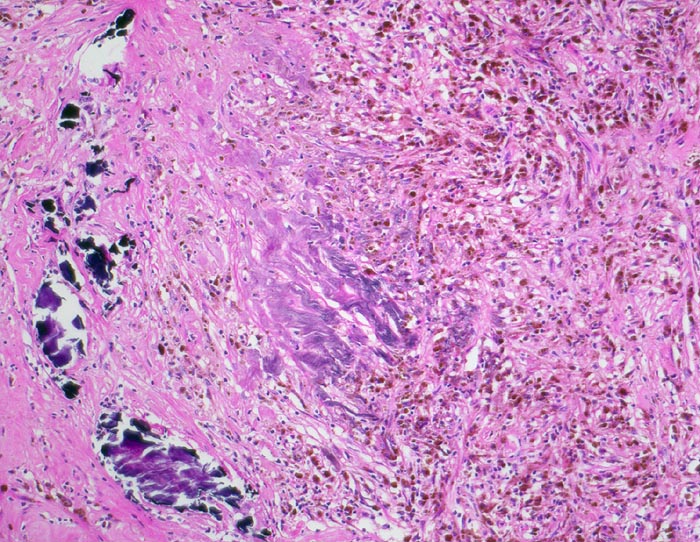

• Wenig zellarmes Tumorstroma mit Blutungsresiduen.

• Solide Tumorzellaggregate eingefasst von dünnen Bindegewebssepten mit zahlreichen dünnwandigen Blutgefässen.

• Frische intratumorale Einblutungen und Blutungsresiduen (Siderinpigment)

• Polygonale Tumorzellen mit reichlich klarzelligem Zytoplasma und deutlichen Zellgrenzen.

• Hyperchromatische, polymorphe grosse Kerne mit prominenten Nukleolen (entspricht einem Grad 3 nach WHO/ISUP).